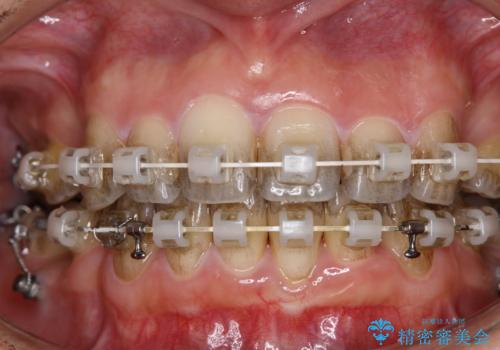

ワイヤー矯正治療中に歯の着色を綺麗に

- ワイヤー矯正治療中にクリーニングを希望されました。

日常的にコーヒーを飲むそうで、装置周りの着色が気になるとのことでした。

エアフロー60分コースを行いました。